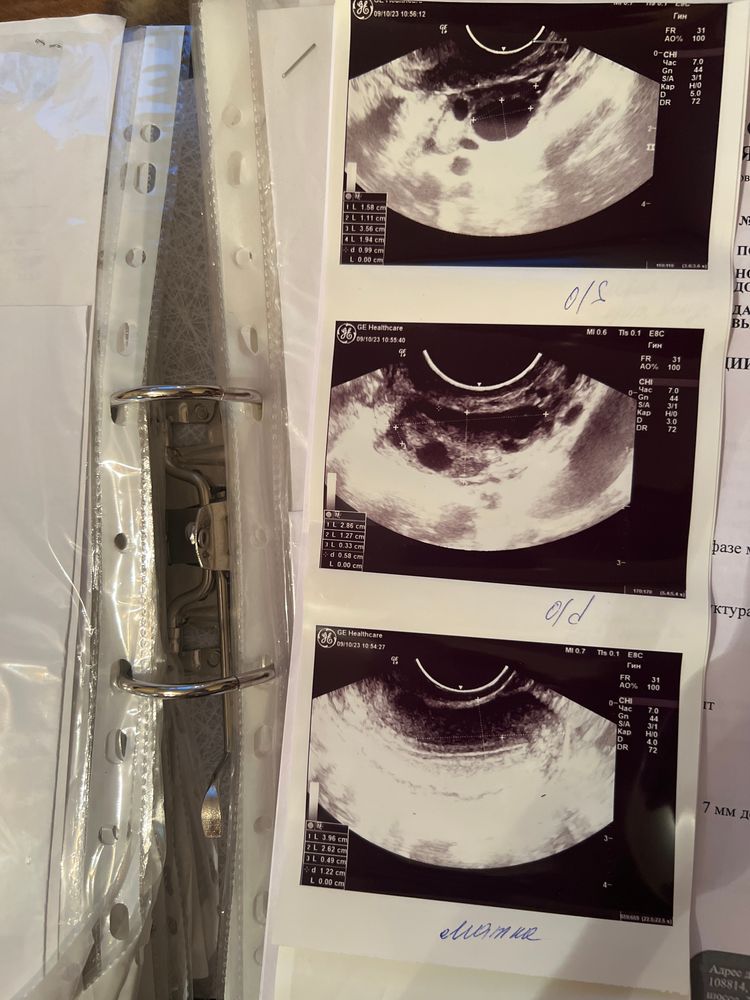

С мужем решили, что хотим ребенка💕 я сходила, проверила кровь, мазок на основные показатели, узи, молочные железы, врач сказала, что все отлично, по узи в этом месяце была в первую фазу цикла, на 10дц. Увидели ДФ 16х11мм, эндометрий 5мм 🥲 мне показался маловат.., Г сказала стараться на днях

нормальный ли эндометрий для такого дня цикла и сам фолликул? Цикл 30 дней, фото узи прикрепляю